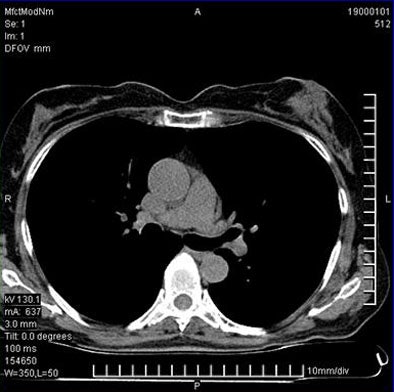

![]() |

| About 16% of firefighters with calcium scores greater than 10 were referred for coronary CTA. Among the patients undergoing CTA, 40 of the 133 (30%) of patients had significant coronary artery disease. All images courtesy of Dr. Matthew Budoff. |